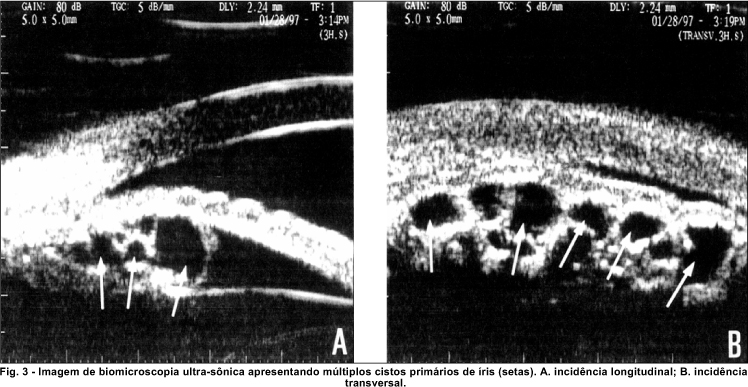

Foram detectados 48 (60%) casos de cistos múltiplos (figura 3) e 32 (40%) de cistos únicos. Não houve diferença significante entre as freqüências para os dois tipos de ocorrência (c2, p=0,094, correção de Yates).